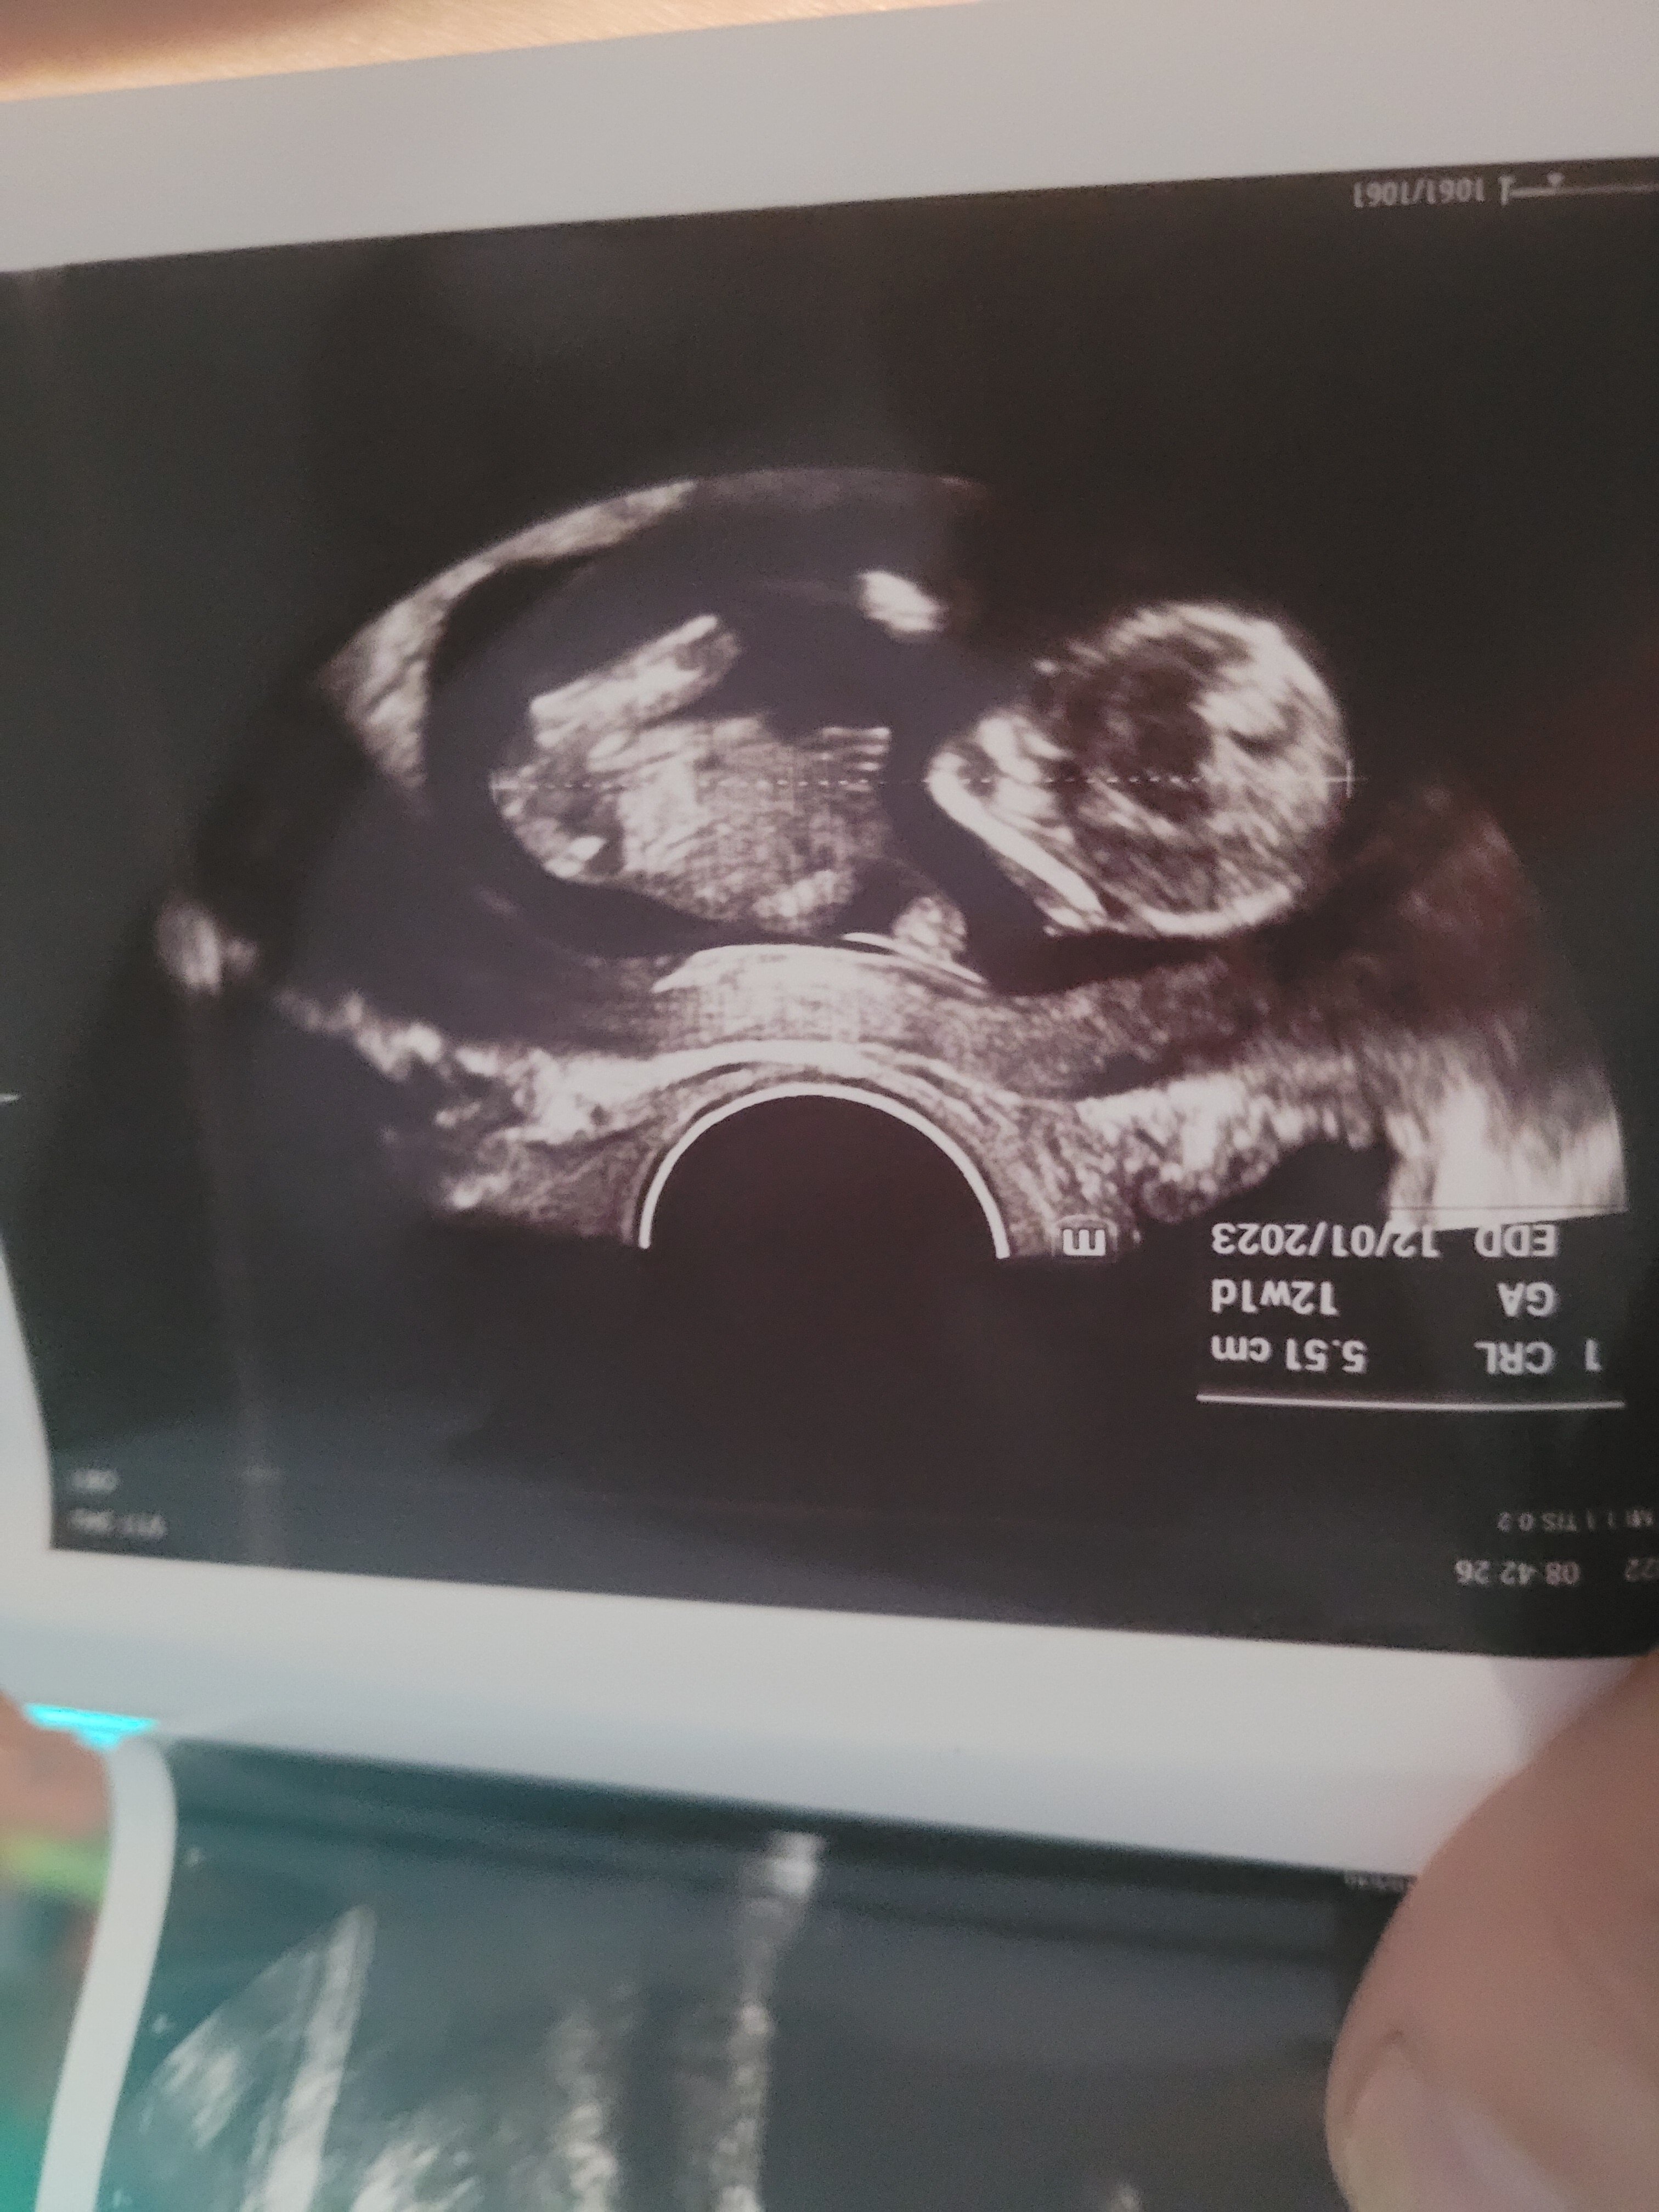

Ciężko stwierdzić. Pokaże ci moje foto z 17 tc zupełnie inne ujęcie . Z tego twojego ciężko cos obstawiać

Załączniki

• 20200128_162413.jpg

20200128_162413.jpg

1,4 MB · Wyświetleń: 1 004